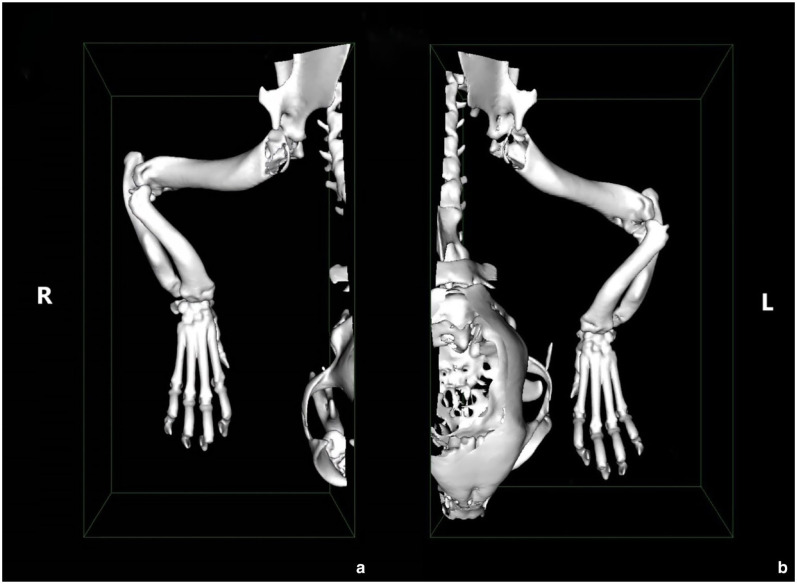

Case summary: A 10-month-old male neutered Dwelf cat with bilateral thoracic angular limb deformity secondary to chondrodystrophism presented with an acute onset of left thoracic lameness due to elbow subluxation and radial head displacement. Financial restrictions limited treatment to a single surgical procedure consisting of a left ulnar osteotomy, radioulnar polypropylene toggle placement and two temporary radioulnar transosseous K-wires. The lameness resolved but a degree of radial head subluxation persisted, radiographically similar in degree to the contralateral limb.